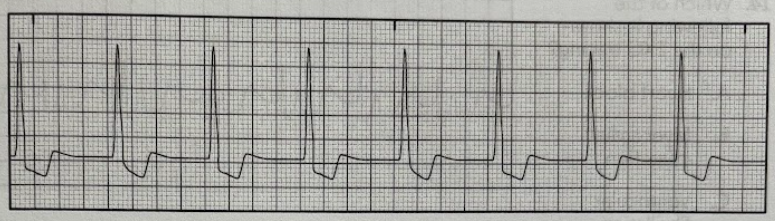

Using the 1500 method, determine the patient’s heart rate from the EKG tracing

A. 85/min

B. 95/min

C. 105/min

D. 115/min

D

Using the 6-second method, determine the patient’s heart rate from the EKG tracing.

A. 60/min

B. 80/min

C. 120/min

D. 140/min

C